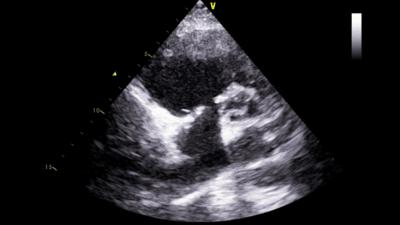

2月26日,终于等到手术的日子。由于患者是二次开胸,我院心脏中心团队格外谨慎小心,全力以赴。术中发现,患者胸部切口和胸骨都有感染,心脏周围粘连非常紧密,仅是开胸和分离心脏周围粘连就用了2个多小时。为患者建立体外循环,打开心脏探查三尖瓣时发现:三尖瓣隔叶仅为残迹,后叶缺如,前叶面积也只有正常一半,而且没有腱索和乳头肌牵拉。发生这样的病变,只有换瓣才能挽救患者的生命。可是三尖瓣瓣环已经被人工成形环固定,心内膜已经把成形环包埋起来,需要先拆掉成形环。但真是说起来容易,做起来难啊。三尖瓣瓣环比较薄,周围还有右冠状动脉和房室结。如果不小心撕坏三尖瓣瓣环,损伤冠状动脉或损伤房室结,都会造成严重并发症。吴清玉教授沉着冷静,凭着丰富的手术经验,顺利地拆除了成形环,置换好新的人工瓣膜。患者心脏复跳,手术堪称完美。由于术前准备充分,术中节血措施完备,整个手术仅使用红细胞4个单位,患者术后12天就顺利康复出院了。